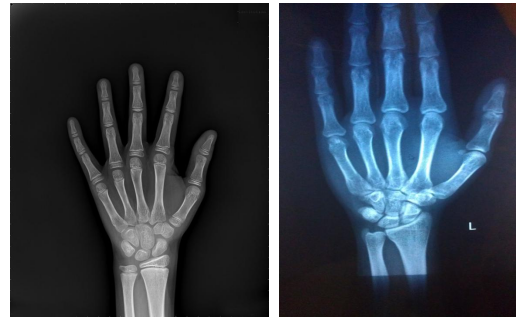

免费拍骨龄

5.免费AI智能拍摄骨龄及成年身高预测

01.什么是骨龄?

骨龄是骨骼年龄的简称,骨龄在很大程度上代表了儿童真正发育水平,因此用骨龄来判定人体成熟度比实际年龄更为确切。

02.医生为什么要测定儿童的骨龄?

骨龄评估能较准确地反映个体的生长发育水平和成熟程度。

它不仅可以确定儿童的生物学年龄,还可以通过骨龄了解儿童的生长发育潜力以及性成熟的趋势。亦可预测儿童的成年身高,骨龄的测定还对一些儿科内分泌疾病的诊断有很大帮助。同时对于一些身材矮小的患者的治疗有指导意义。

03.青少年一般什么时候骨骺闭合?

女孩在青春期11-15岁发育最快,一般骨骺完全闭合在15~17岁,

男孩在青春期12-16岁发育最快,一般骨骺完全闭合是在16~18岁。